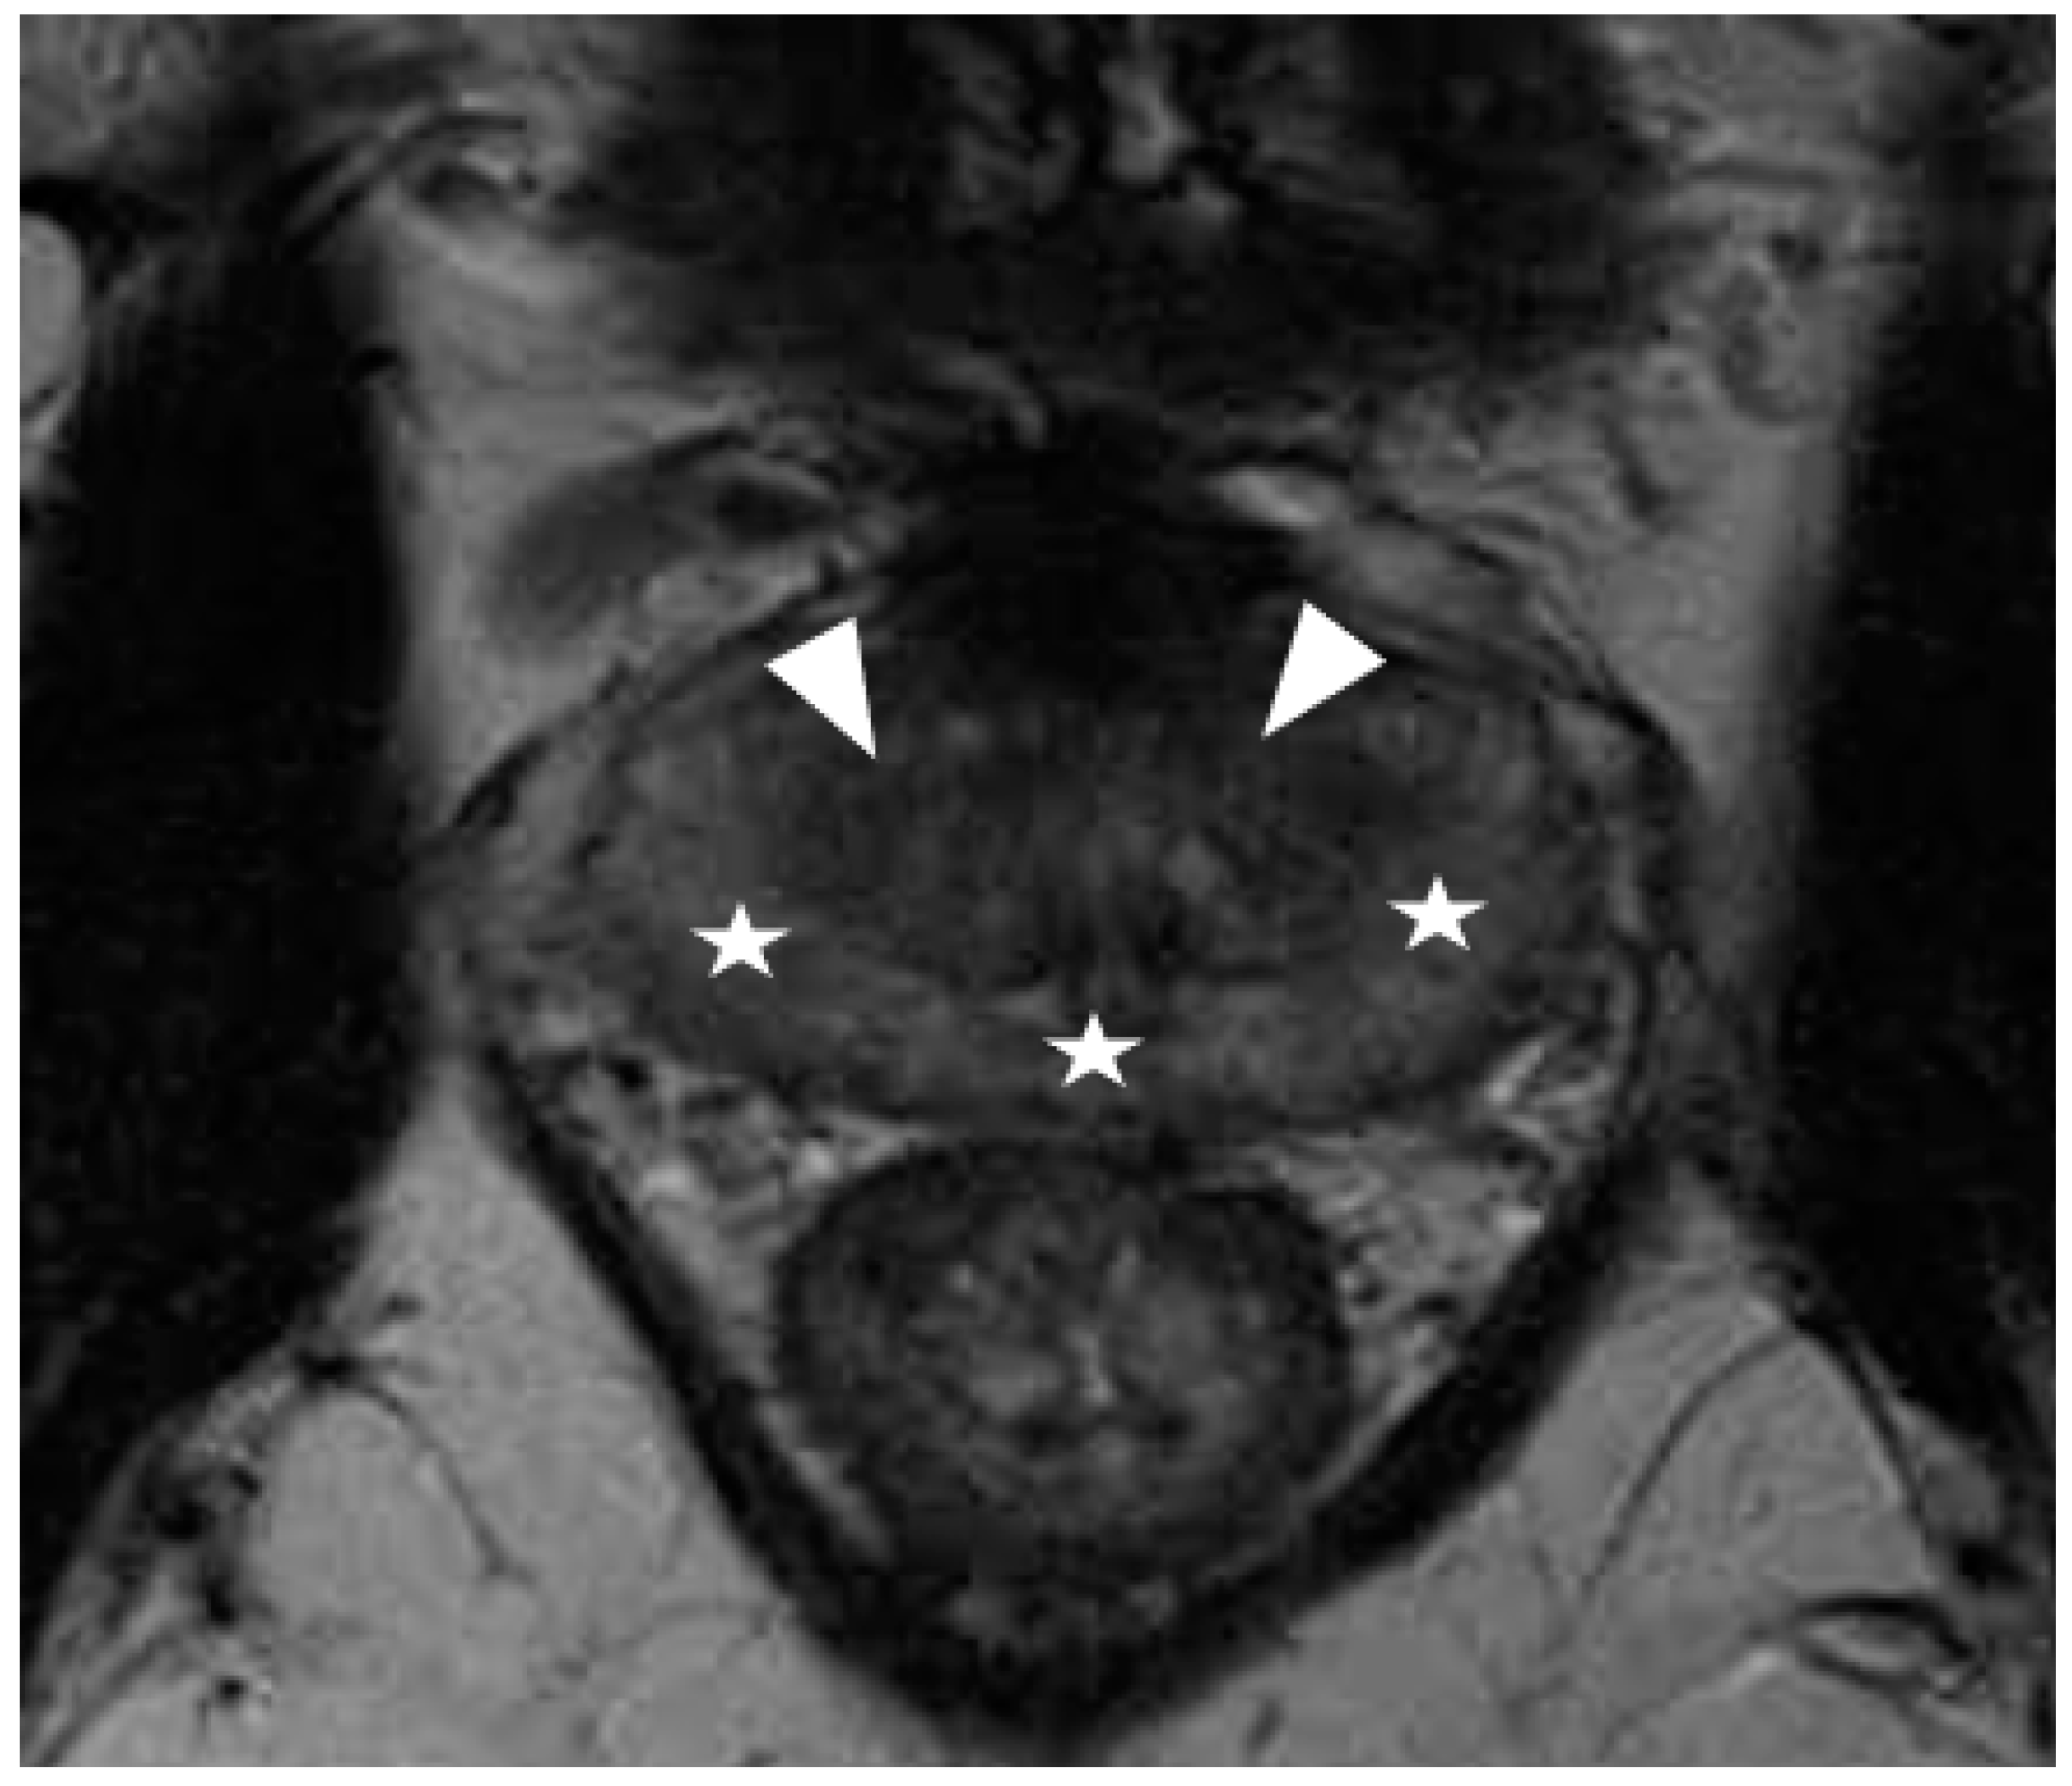

Recently, several studies have compared different deep CNN models on zonal segmentation. Cuocolo et al. [48] compared three deep learning methods, UNet, an efficient neural network (ENet) [60], and efficiently residually factorize ConvNet (ERFNet) [61] in the PROSTATEx public dataset. ENet (0.91, 0.87, 0.71) and UNet (0.88, 0.86, 0.70) were more accurate than ERFNet (0.87, 0.84, 0.65) in terms of DSC (for WG, TZ and PZ, respectively), while ENet outstood the other two methods, with faster convergence speed and fewer parameters. Saunders et al. [49] compared the performance of independent training, transfer learning, and aggregated learning based on 3D and 2D U-Net models, on the premise of limited training data. In addition, 3D U-Net was found to be more robust to a small sample size (five training cases) than 2D U-Net by an average DSC of 0.18, while transfer learning and aggregated learning (similar DSC: 0.73, 0.83, 0.88 for PZ, CG, WG, respectively) both outperformed independent training (DSC 0.65, 0.77, 0.83) when using five internal training cases. Predictably, automated segmentation between PZ and TZ can become challenging in cases where tumours span across both zones, since false positives like prostatitis in the PZ reduce its normal high T2 signal to become isointense to the TZ, whereas severe benign prostatic hypertrophy in the TZ compresses the PZ, reducing the ability to discriminate between the two zones (Figure 2, Figure 3 and Figure 4).

Figure 3.

Prostatitis typically appears as diffuse hypointensity in the peripheral zone on T2-weighted imaging (star), resulting in an almost similar signal to stromal nodules related to benign prostatic hyperplasia in the transition zone (arrowhead). This may make differentiation between peripheral and transition zone difficult, and zonal segmentation challenging.